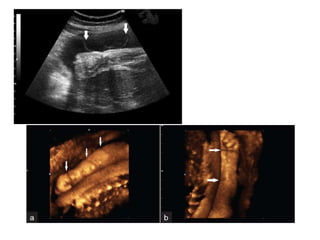

Meckel-Gruber Syndrome

Renal cystic dysplasia 95-100%

Encephalocele 60-80%

Postaxial polydactyly 55-75%

2nd trimester oligohydramnios

Significantly increased abdominal circumference

***AR =25% recurrence risk

MKS1 17q21-24, MKS2 11q13, MKS3 8q24